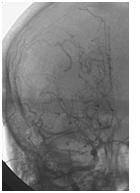

Mujer de 46 años que ingreso por cefalea súbita, hemiparesia izquierda y disartria, con tomografía axial computarizada cerebral simple que mostró hemorragia frontoparietal derecha drenada a ventrículos y arteriografía con patrón Moyamoya. Reingreso 3 meses después con deterioro del estado de consciencia y tomografía axial computarizada cerebral simple que mostró hemorragia intraparenquimatosa temporoparietal izquierda con extensión intraventricular y desviación de la línea media, se manejo en Unidad de Cuidados Intensivos con traqueostomía y gastrostomía, presentó neumonía y sepsis nosocomial, finalmente falleció en la Unidad de Cuidados Intensivos.